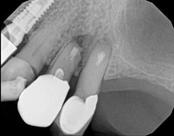

Non-surgical root canal treatment:

6-month follow-upThis patient presented with pain when chewing. Diagnostic testing was done and determined it was the lower molar. The diagnosis was: pulpal necrosis, symptomatic periradicular periodontitis. Root canal treatment was performed with laser disinfection. The tooth had a crown and we accessed the tooth through the crown. We saved the tooth and the crown.